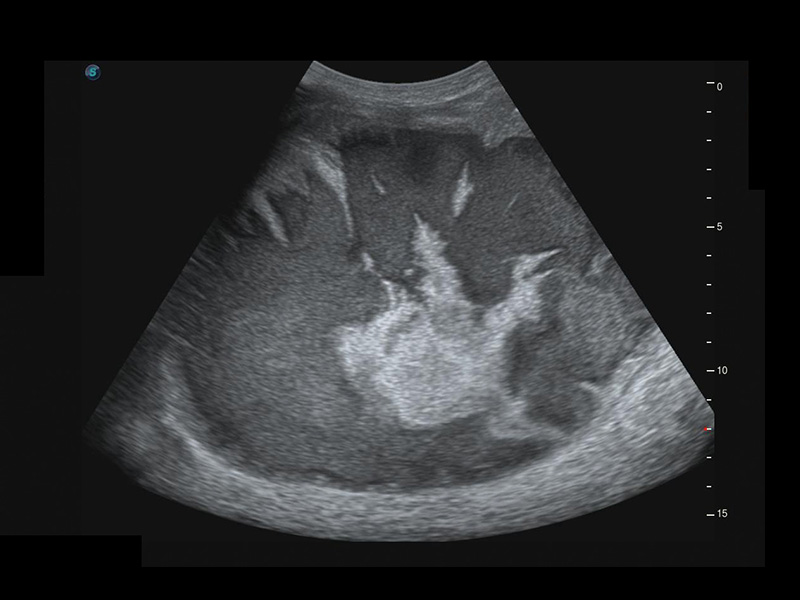

S-Fetus*

S-Fetus è uno strumento di facile utilizzo che consente il rilevamento completamente automatico e preciso dei piani più significativi e delle misurazioni della biometria fetale, utilizzate frequentemente. Con la modalità cine-loop della testa del feto, S-Fetus è in grado di estrarre i piani standard e visualizzare i risultati della misurazione in un secondo, riducendo notevolmente Il numero di battute e i tempi di lavoro necessari. È progettato per trasformare gli esami ecografici ostetrici in un'esperienza molto più comoda, veloce e piacevole.

1 OFD(HC): 87,03 mm

HC: 251,00 mm

GA: 27w 1d

HC/AC: 96,13%

2 BPD: 70,56 mm

GA: 28 w 2d

S-Fetus(acq.)

& S-Fetus(meas.)